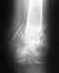

Re: Несращение большеберцовой кости

Желательно внятно указать все даты. Когда сделан остеосинтез, когда сделан этот снимок.

Вообще, если к полугоду нет сращения, надо делать реостеосинтез с рассверливанием. То есть менять стержень на больший по диаметру. Ничего из таза брать не надо. Вариант с пластиной - более трудоемкий, длительный и рискованный. Есть и много других вариантов.